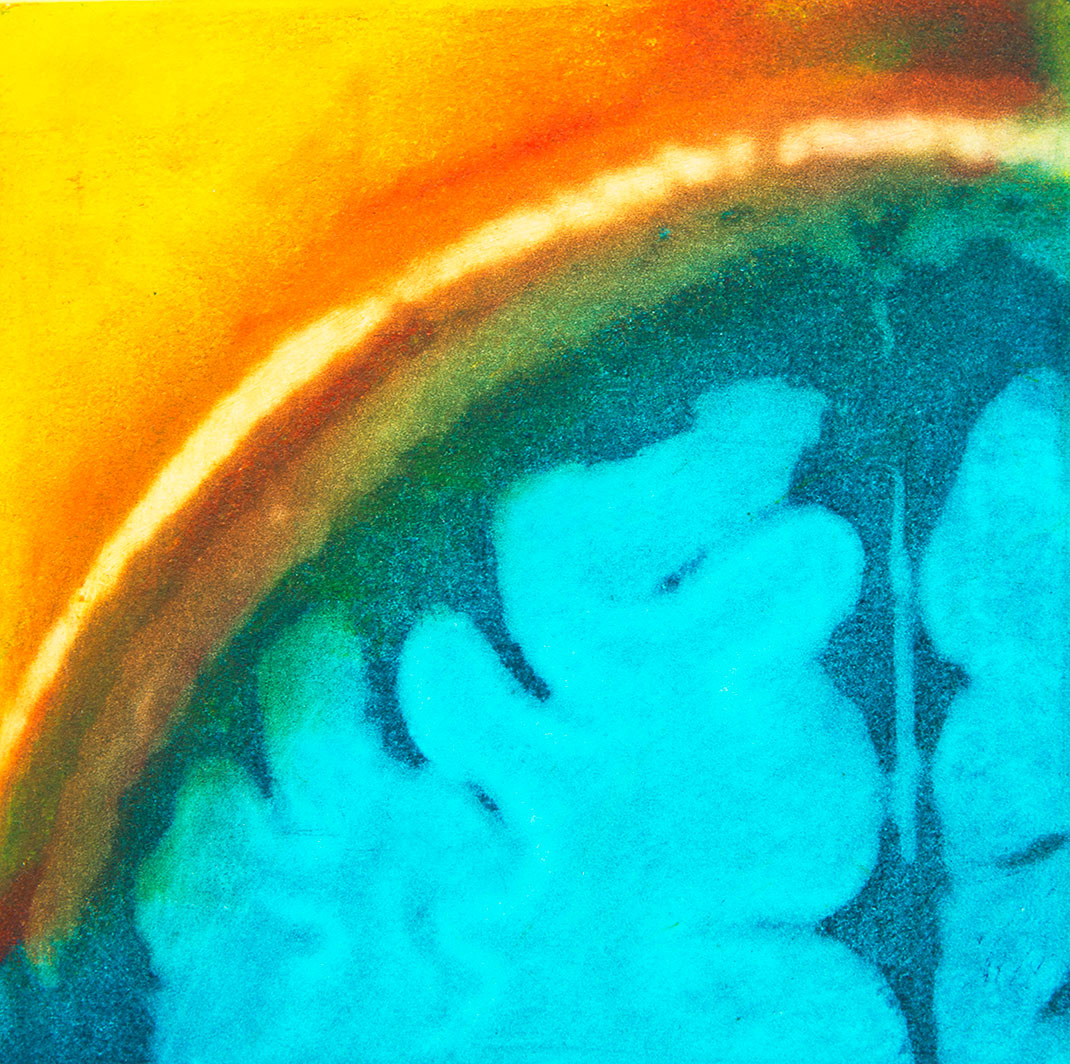

Elle trouve alors sa source d’inspiration dans sa maladie à travers ses IRMs. « Mes nombreux traitements m’ont donné envie de réinterpréter l’imagerie médicale. Les patients, souvent anxieux, ne voient que laideur et effroi dans les pixels noirs et gris des IRMs. J’ai alors ressenti le besoin vital de les utiliser pour montrer les merveilles et la beauté de nos cerveaux, y compris ceux souffrant d’une maladie. Je veux guérir les patients de la peur de regarder leurs IRMs », s’émeut Elizabeth.

En réutilisant ses scanners, Elizabeth Jameson cherche à insuffler des émotions et des sentiments dans la froideur technologique. Pour cela, elle utilise de nombreux supports : la peinture sur soie ou encore des impressions à partir de gravures sur cuivre ou sur plaque solaire. Ensuite, elle renforce la couleur de ses images grâce à de la peinture, des crayons ou du pastel sec. Le résultat offre une collection brillante, colorée, pleine d’émotion et de symbole.

Maintenant tétraplégique, Elizabeth crée avec l’aide d’un assistant. Selon elle, ses impressions ne sont pas qu’un moyen de faire la chronique des changements de son cerveau, qu’elle qualifie d’« organe le plus sacré ». Son travail est également un moyen de devenir plus familière avec ces changements, pour les rendre moins terrifiants. « Mon art est composé à 90 % de mon cerveau, tout simplement parce que je suis mon cerveau », conclut-elle.